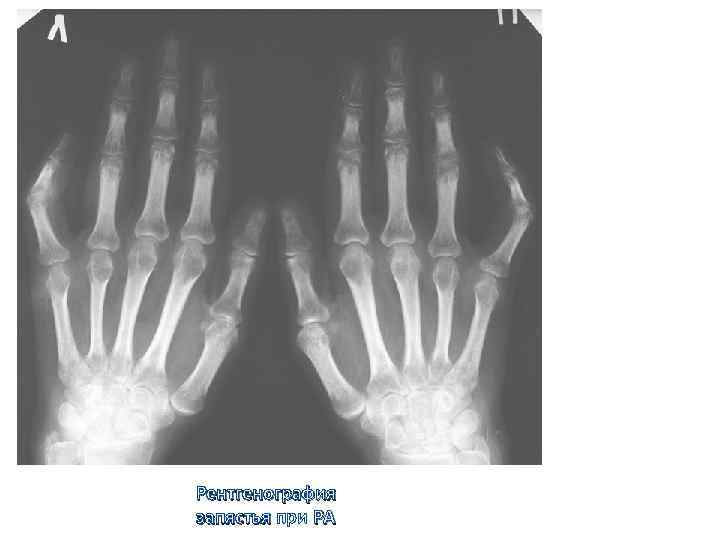

Критерии диагноза ревматоидного артрита Американской ревматологической ассоциации (1987). Наличие, по крайней мере, 4 из Критерии диагноза ревматоидного артрита Американской ревматологической ассоциации (1987). Наличие, по крайней мере, 4 из следующих признаков: -утренняя скованность более 1 часа; -артрит 3 и более суставов; -артрит суставов кистей; -симметричный артрит; -ревматоидные узелки; -положительный ревматоидный фактор; -рентгенологические изменения.

Рентгенография запястья при РА Рентгенография запястья при РА